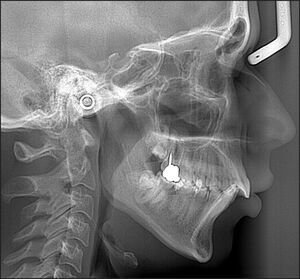

A study by Casko and Shepherd showed that there is a broad range of ANB angles representative of naturally occurring, sagittal, intermaxillary relationships that ranged from -3 - +8 degrees.7,8 These findings were confirmed and further expanded on by Kim,9 who divided normally occurring skeletal patterns into 9 types after mathematically modelling the skeletal patterns that occurred in subjects with Class I occlusion. The 9 types were based on antero-posterior skeletal cephalometric measurements that predict skeletal Class I, II, and III, combined with vertical skeletal cephalometric measurements that predict hyper-, normo-, and hypo-divergent skeletal types. Figures 4A, 4B and 4C.

This study confirmed that dental relationships compensate for the diversity of skeletal patterns, with skeletal Class I and the normo-divergent vertical skeletal type found in 13.9% of subjects. The highest prevalence was skeletal Class III with normo-divergent vertical types (25.5%), followed by skeletal Class II hyperdivergent vertical types (17.7%).8 Thus, dentoalveolar Class I patients can be associated with normo-, hyper-, and hypo-divergent skeletal vertical types. See Figure 5AB.